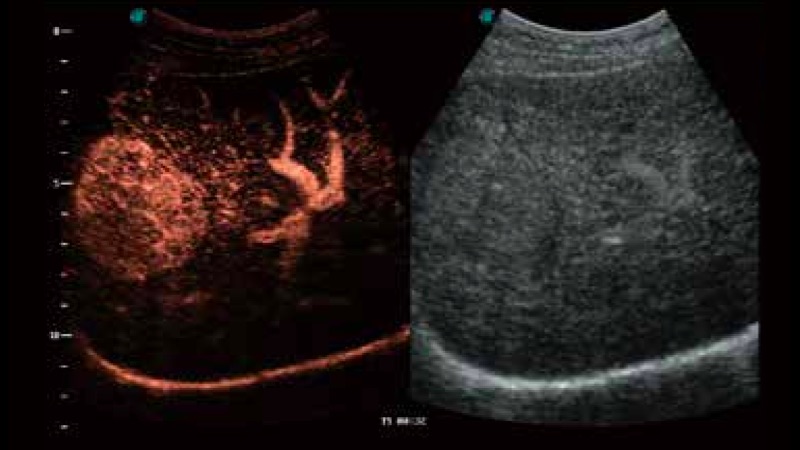

S-Live 高分辨率容积成像

通过仿真成像技术对3D/4D立体数据进行渲染,多种初始光源位置可选,并支持轨迹球360°光源位置自由调节,清晰显示不同方位容积图像细节。